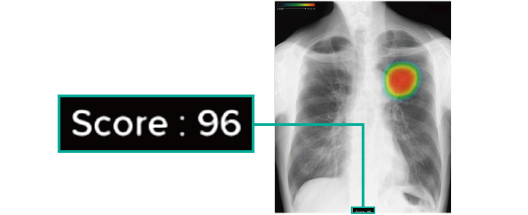

スコア表示

0~100に分けられた確信度スコアの最大値が数値として表示されます。